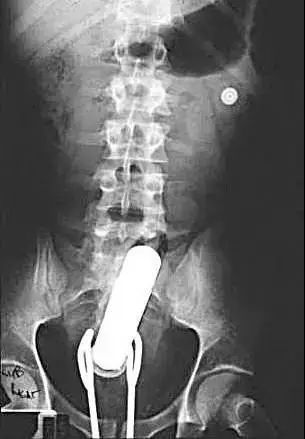

如果这一招还不行的话,那患者可能就会受点罪了。这时候可以采取剖腹探查术,打开患者的腹腔,探查异物在肠道里的位置。如果可行的话,一边挤压着肠子,一边从肛门取异物,成功率也是蛮高的。

如果以上的一切办法都不管用的话,医生就得切开肠子去取出异物来了。而这个,是医生和患者都最不愿意看到的情形。